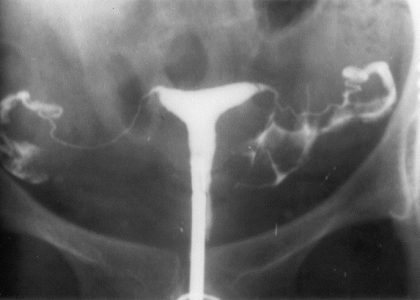

HSG is a special X-ray examination which looks at the inside of your womb (uterus)